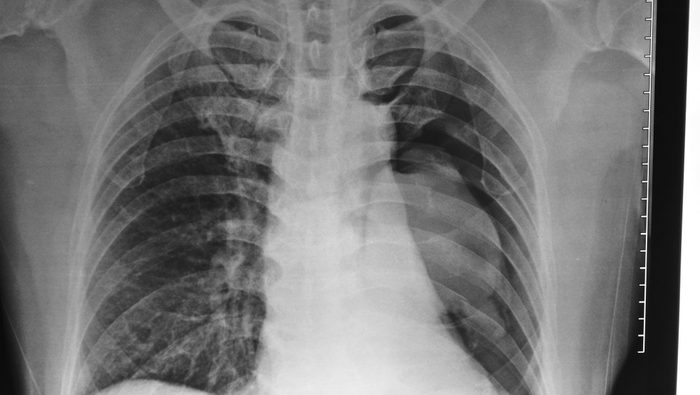

One month later: Lungs begin to show how much healthier they are

Smokers often have a nagging cough or make a wheezing sound when they breathe that many refer to as a smoker’s cough. Smoking even e-cigarettes can badly impair your lung health and make fighting off infections difficult. Quitting, however, will help your lungs rebound. “After one month, your lung capacity improves; there’s noticeably less shortness of breath and coughing,” Dr. Djordjevic says.

After nine months: Your lungs can fight infections again

“After nine months, lung health improves significantly thanks to the renewal of microscopic hair-like structures inside the lungs that help push out mucus and fight infections,” Dr. Djordjevic says. This could significantly reduce your likelihood of some infections and complications from illnesses like the flu and pneumonia.